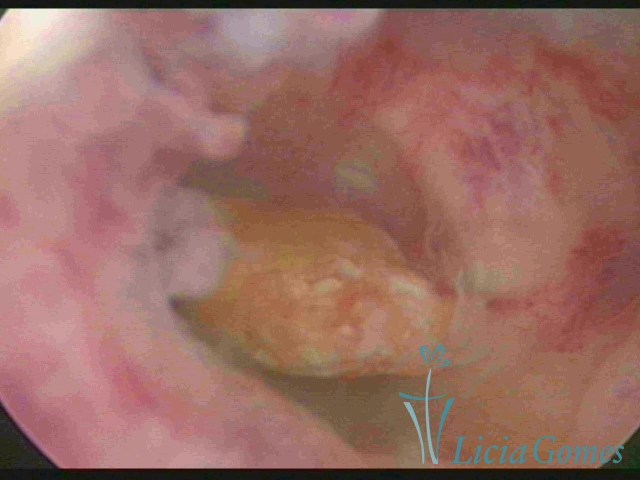

Resíduo do material do DIU solto em cavidade uterina

×